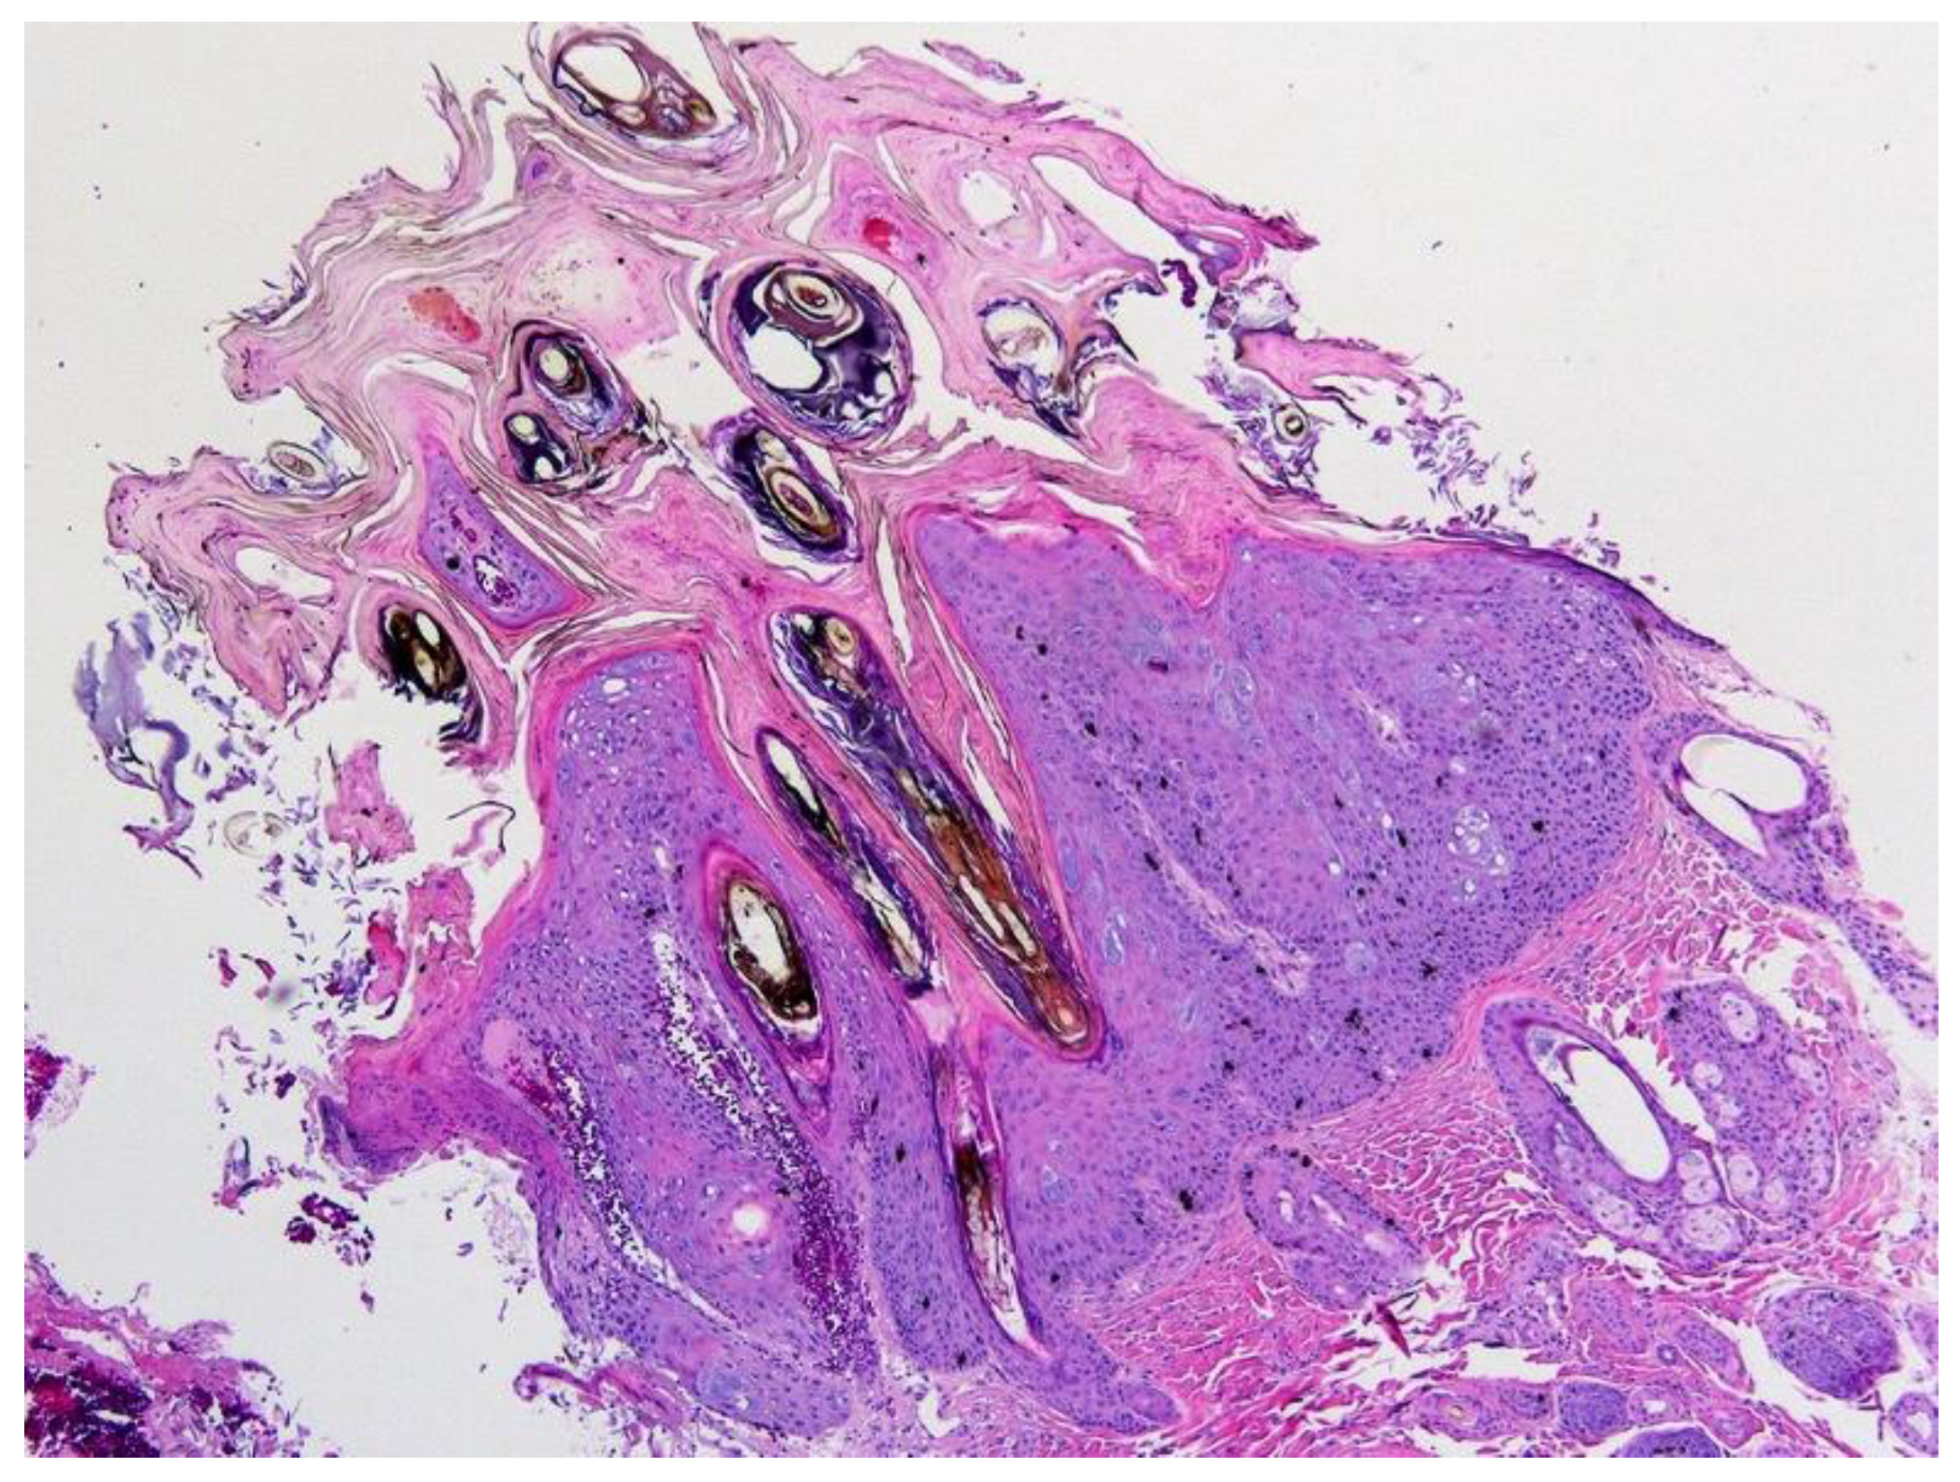

6.2. Canine Viral Cutaneous Plaques

6.3. Papillomavirus-Associated Neoplasia in Dogs

7.2. Feline Viral Cutaneous Plaques